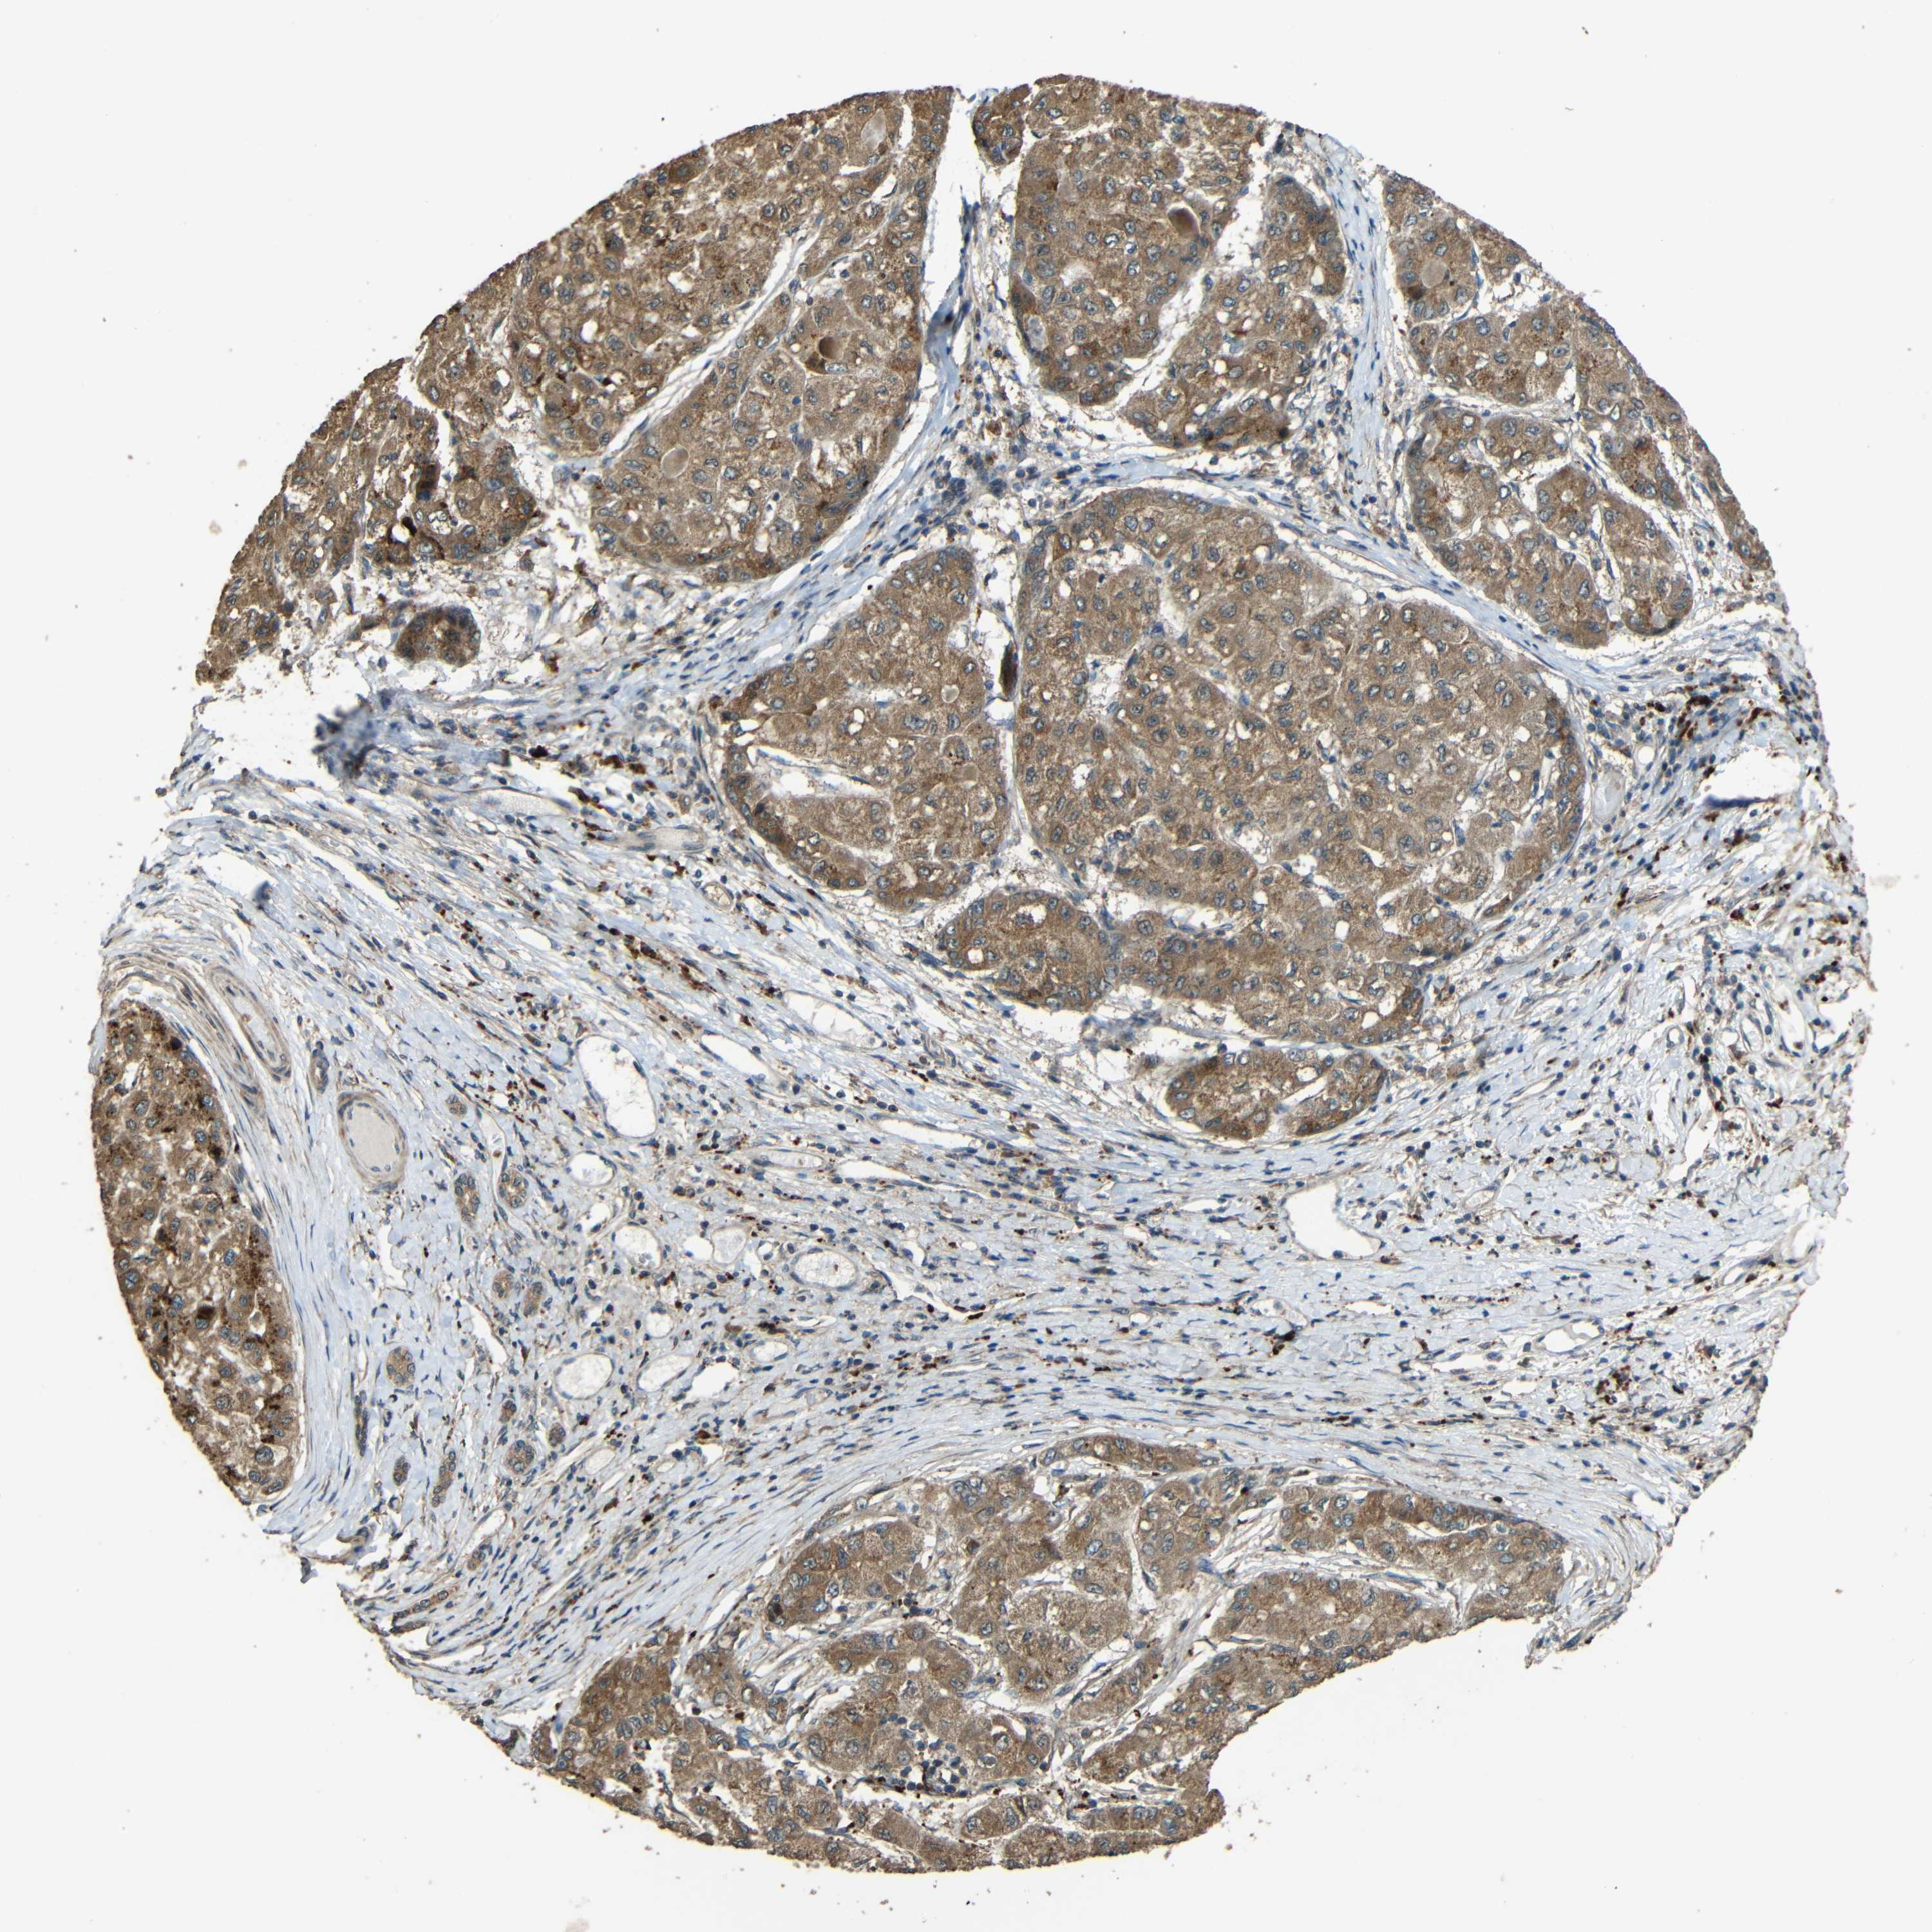

LIVER CANCER - Protein expressioni

A mouse-over function shows sample information and annotation data. Click on an image to view it in a full screen mode. Samples can be filtered based on level of antibody staining by selecting one or several of the following categories: high, medium, low and not detected. The assay and annotation is described here.

Note that samples used for immunohistochemistry by the Human Protein Atlas do not correspond to samples in the TCGA dataset.

Antibody stainingi

Antibody staining in the annotated cell types in the current human tissue is reported as not detected, low, medium, or high, based on conventional immunohistochemistry profiling in selected tissues. This score is based on the combination of the staining intensity and fraction of stained cells.

Each image is clickable and will lead to virtual microscopy that enables deeper exploration of all samples and also displays staining intensity scores, fraction scores and subcellular localization as well as patient and tissue information for each sample.

Antibody HPA063018

Antibody CAB013715

Staining

High

Medium

Low

Not detected

Intensity

Strong

Moderate

Weak

Negative

Quantity

>75%

75%-25%

<25%

None

Location

Nuclear

Cytoplasmic/membranous

Cytoplasmic/membranous,nuclear

Carcinoma, Hepatocellular, NOS

Cholangiocarcinoma